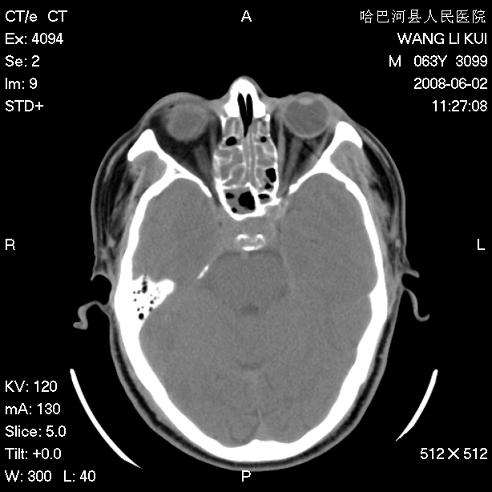

标题: CT13803:反复性鼻塞、流涕一年余 [打印本页]

标题: CT13803:反复性鼻塞、流涕一年余

副鼻窦炎,右上额窦积脓。左眼肌锥内见致密影,视神經受压

全组副鼻窦炎 肌锥内高密度灶。建议进一步检察检查

1、全组副鼻窦炎。

2、左眼眶肌锥内病变,小血管瘤?建议增强。

1)全副鼻窦炎(左侧上颌窦黏膜下囊肿或息肉)。2)左眼眶肌锥内不规则小结节状软组织密度影;考虑为小血管瘤可能。建议行ct增强扫描检查。

全组副鼻窦炎,左侧肌锥内不规则形软组织肿块影,与眼外肌密度相当,左侧视神经受压,肿块与视神经及眼外肌分界清晰,眼外肌无增粗,眶壁无破坏,球后脂肪间隙不模糊,考虑良性改变,小血管瘤或神经源性肿瘤可能,建议增强扫描。

谢谢,增强扫描做了,眶内病灶与海绵窦同步明显强化,血管瘤